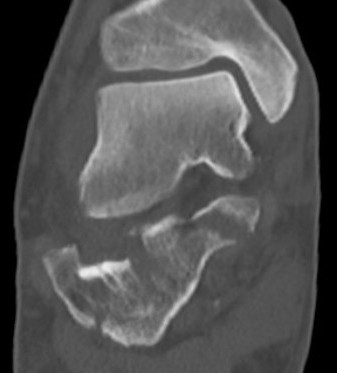

CT scan

| Coronal | Sagittal | Axial |

|---|---|---|

|

Posterior facet / number of fragments Sustenaculum tali Heel widening |

Bohlers angle Posterior facet depression / angulation |

Calcaneocuboid joint Sustenaculum tali |

|

|

|

|

|

|